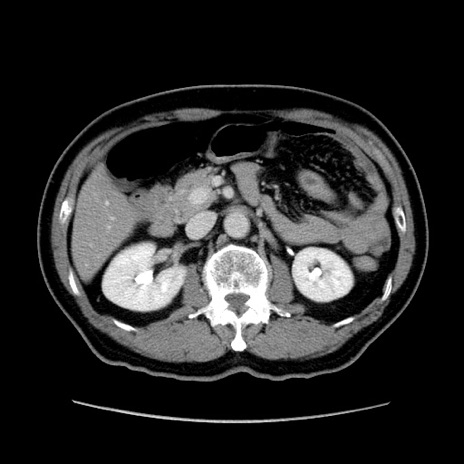

症例34(横断像)

【症例】60歳代 男性

【主訴】右鼠径部膨隆

【現病歴】1年程前より右鼠径部膨隆あり。自己にて還納可能だったため放置していた。3時間前より右鼠径部の脱出を認め、還納困難となり受診。

【既往歴】高血圧

【身体所見】右鼠径部に小児頭大の膨隆あり。弾性硬であり、用手還納は困難。左鼠径部にも膨隆を認める。脱出はなし。

【データ】WBC 15500、CRP 測定なし